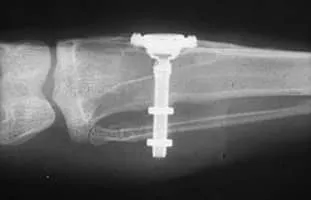

Per-Ingvar Brånemark was a Swedish physician and research professor, acknowledged as the "father of modern dental implantology". The Brånemark Osseointegration Center, named after its founder, was founded in 1989 in Gothenburg, Sweden.